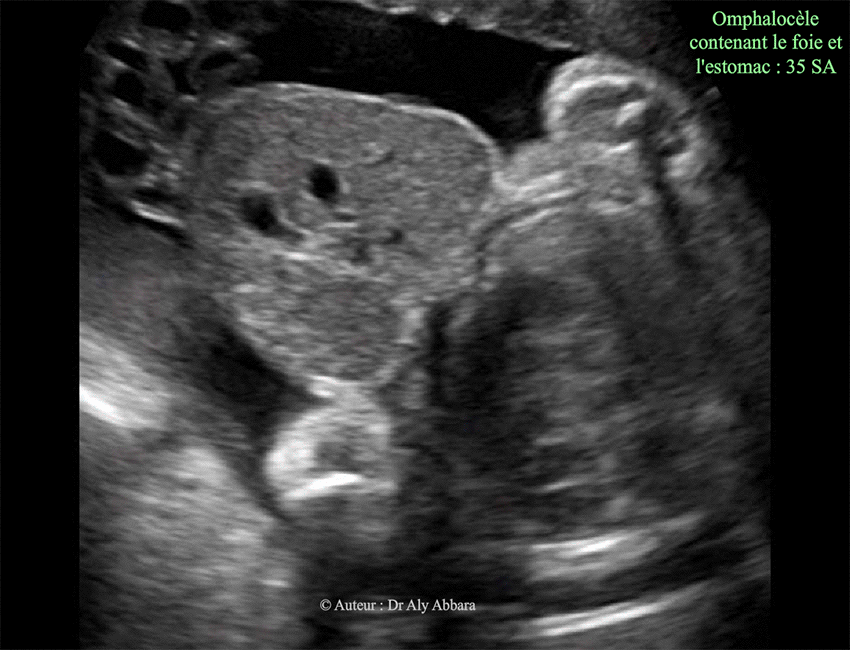

Omphalocèle - Grossesse de 35 SA

Image échographique montrant une grossesse de 35 SA caractérisée par la présence d'une volumineuse omphalocèle contenant la totalité du foie et sa vésicule biliaire, puis l'estomac (visible sur d'autre coupe). L'insertion du cordon ombilical se situe sur la surface extérieure l'omphalocèle. Aucune anomalie morphologique associée et décelable à l'échographie. Le caryotype fœtal ne montre pas d'anomalie chromosomique associée (46, XX).